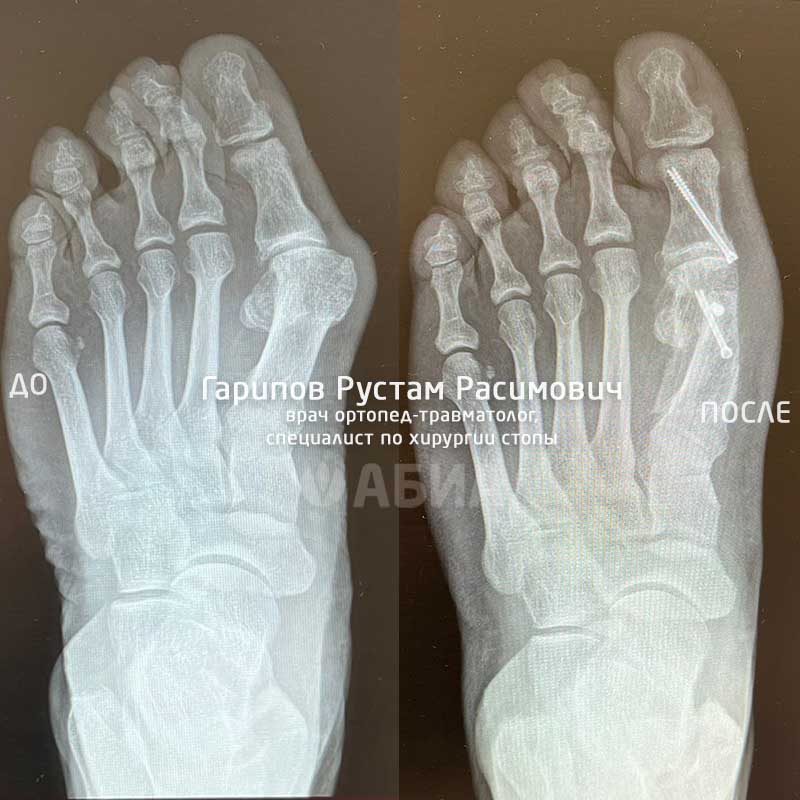

Одно из приоритетных направлений деятельности Рустама Расимовича - хирургия стопы по современным методикам Weil, Chevron, Scarf, Bosch, Akin и др.

Доктор выполняет операции при Hallux Valgus, Hallux Rigidus, Hallux Varus и других заболеваниях и деформациях стопы.